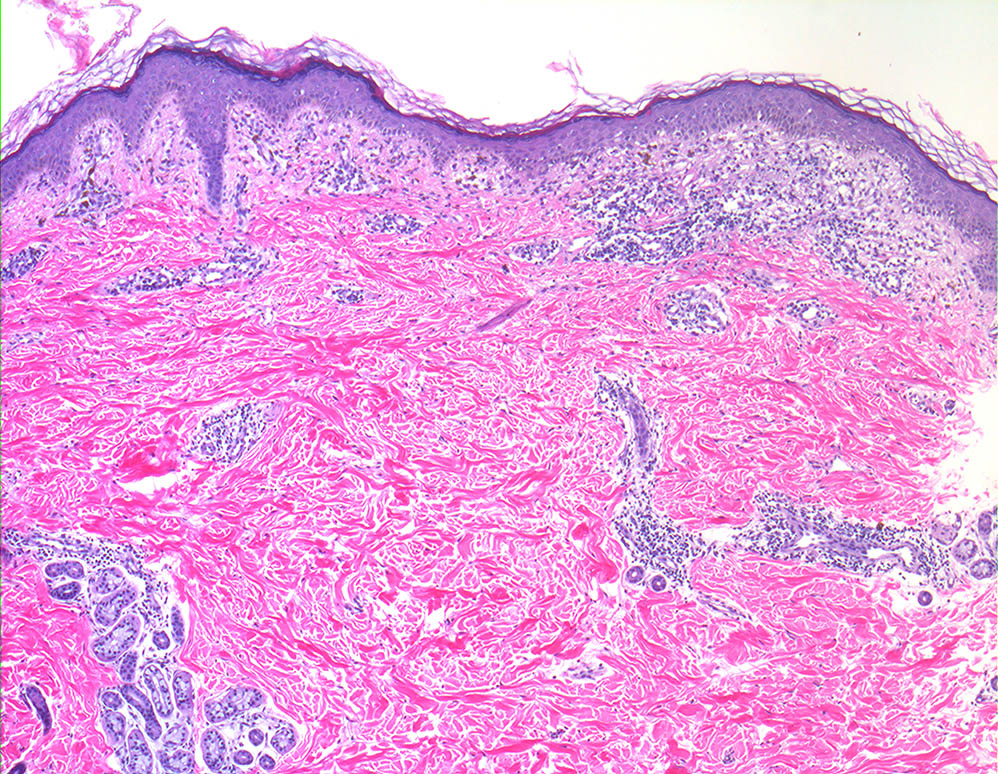

Ashy dermatosis = التهاب الجلد الرمادي